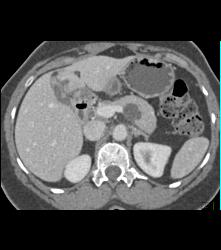

Diagnosis

Intraductal Papillary Mucinous Neoplasm (IPMN)